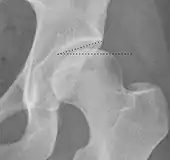

| Tönnis angle | ![]() |

Slope of the sourcil (the sclerotic weight-bearing portion of the acetabulum) | 0 to 10°

|

| Caput-sourcil angle[21] | ![]() |

Superior to the Tönnis angle in cases without joint space narrowing or subluxation.[21] The medial point of the sourcil is at the same height as the most superior point of caput femoris. | −6 to 12°[21]